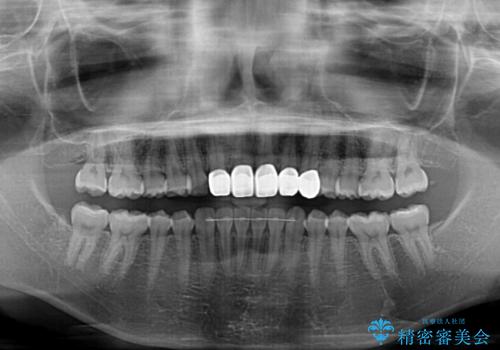

- 前歯の歯並びと虫歯を気にして来院された患者様です。

上下前歯の歯列不正はインビザラインにより歯列を整え、その後に、前歯5本をオールセラミッククラウンにて補綴治療することとしました。

矯正治療前に前歯のむし歯治療を行ったものの、樹脂で充填するには虫歯が広範囲であったため、審美的に問題がありました。

矯正治療にて歯並びを整えた後に、虫歯の大きかった5本の歯をセラミッククラウンにて補綴し、明るい口元になりました。